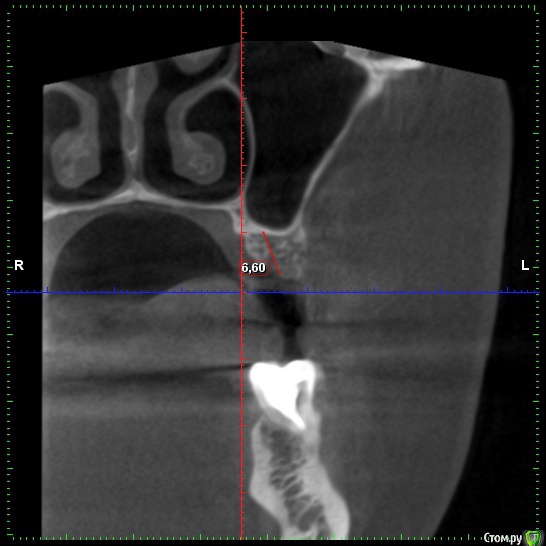

zubovolok Опубликовано 3 января, 2019 Поделиться Опубликовано 3 января, 2019 (изменено) Коллеги подскажите пожалуйста, планируется установить имплант супер лайн длинной 7мм,то есть 6.5,должно быть в кости, возможно ли в данных условиях обойтись без закрытого синуса? Или лучше поднять и на сколько? Изменено 3 января, 2019 пользователем zubovolok Ссылка на комментарий

Nazim_NV86 Опубликовано 3 января, 2019 Поделиться Опубликовано 3 января, 2019 У вас там нет 6.5мм для имплантата. Поднимайте на 2мм синус и ставьте 7 заглубив его нормально. 2 Ссылка на комментарий